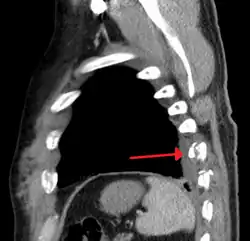

-

Two broken ribs as seen on parasagittal CT

Plain X-rays often pick up displaced fractures but often miss undisplaced fractures.[13] CT scanning is generally able to pick up both types of fractures.[13]